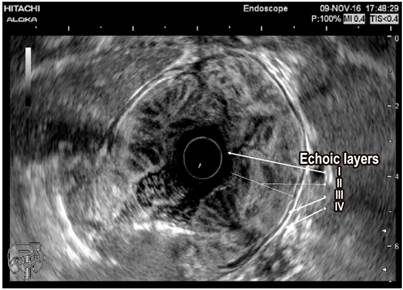

Paraclinical tests including a complete blood count, albumin, nitrogen and urine analysis were requested. The patient was found to have normocytic, normochromic, heterogeneous anemia. His hemoglobin level was 11.2 g/dL, his serum albumin level was 2.8 g/dL, and his creatinine level was 0.8 mg/dL (normal). The urine analysis did not find proteinuria. Given the clinical, paraclinical and endoscopic findings, computed tomography (CT) of the abdomen was performed. It found thickened gastric walls with diffuse, marked and symmetric gastric folds without evidence of nodular lesions. The maximum thickness was 53 mm (Figure 1). Findings from gastric endoscopic ultrasonography (EUS) were similar to those described of the upper digestive tract endoscopy, but thickening of the gastric wall dependent on the first and second echoic layers (mucosa and muscular mucosa, respectively) was found. Anechoic spaces were found in the second echoic layer respecting the third and fourth echoic layers (submucosa and muscularis propria, respectively) (Figure 2).

Differential diagnosis revolves around other entities that thicken gastric folds. These include lymphocytic gastritis, polyposis syndromes, hyperplastic polyps, plastic lymphadenitis and lymphoma (Table 1). EUS is a useful tool for differential diagnosis since it can exclude a thickening of vascular origin in cases where biopsies may cause significant bleeding. Consequently, it is recommended that EUS precede any decision to take biopsies in cases of thickening of gastric folds. Thickening originating in the second echoic layer supports a diagnosis of Menetrier’s disease (Figure 2). 6,7